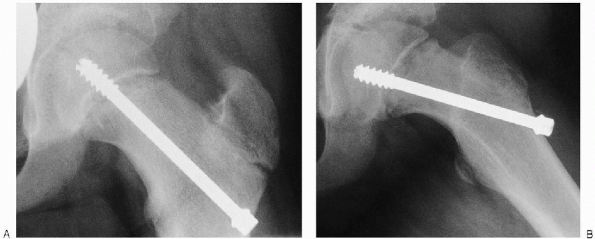

![]() |

FIGURE 24-6. Image intensifier views of the guide wire in the correct position in the anteroposterior (A) and lateral (B) planes. The guide wire is perpendicular to the physis and in the center of the femoral head. Radiographs (C, D) with a drawn black bar simulating the proper position of the guide wire and therefore the correct position for the hip pin.

position of the pin is checked in the anteroposterior and lateral

planes. The cannulated drill is placed over the guide wire, and

drilling is started. As the drill is withdrawn, a hemostat is placed on

the guide wire so it does not come out of the wound. The hip pin is

then placed over the guide wire and advanced with the T-handle wrench.

If the position is satisfactory, the guide wire is withdrawn (Fig. 24-12).